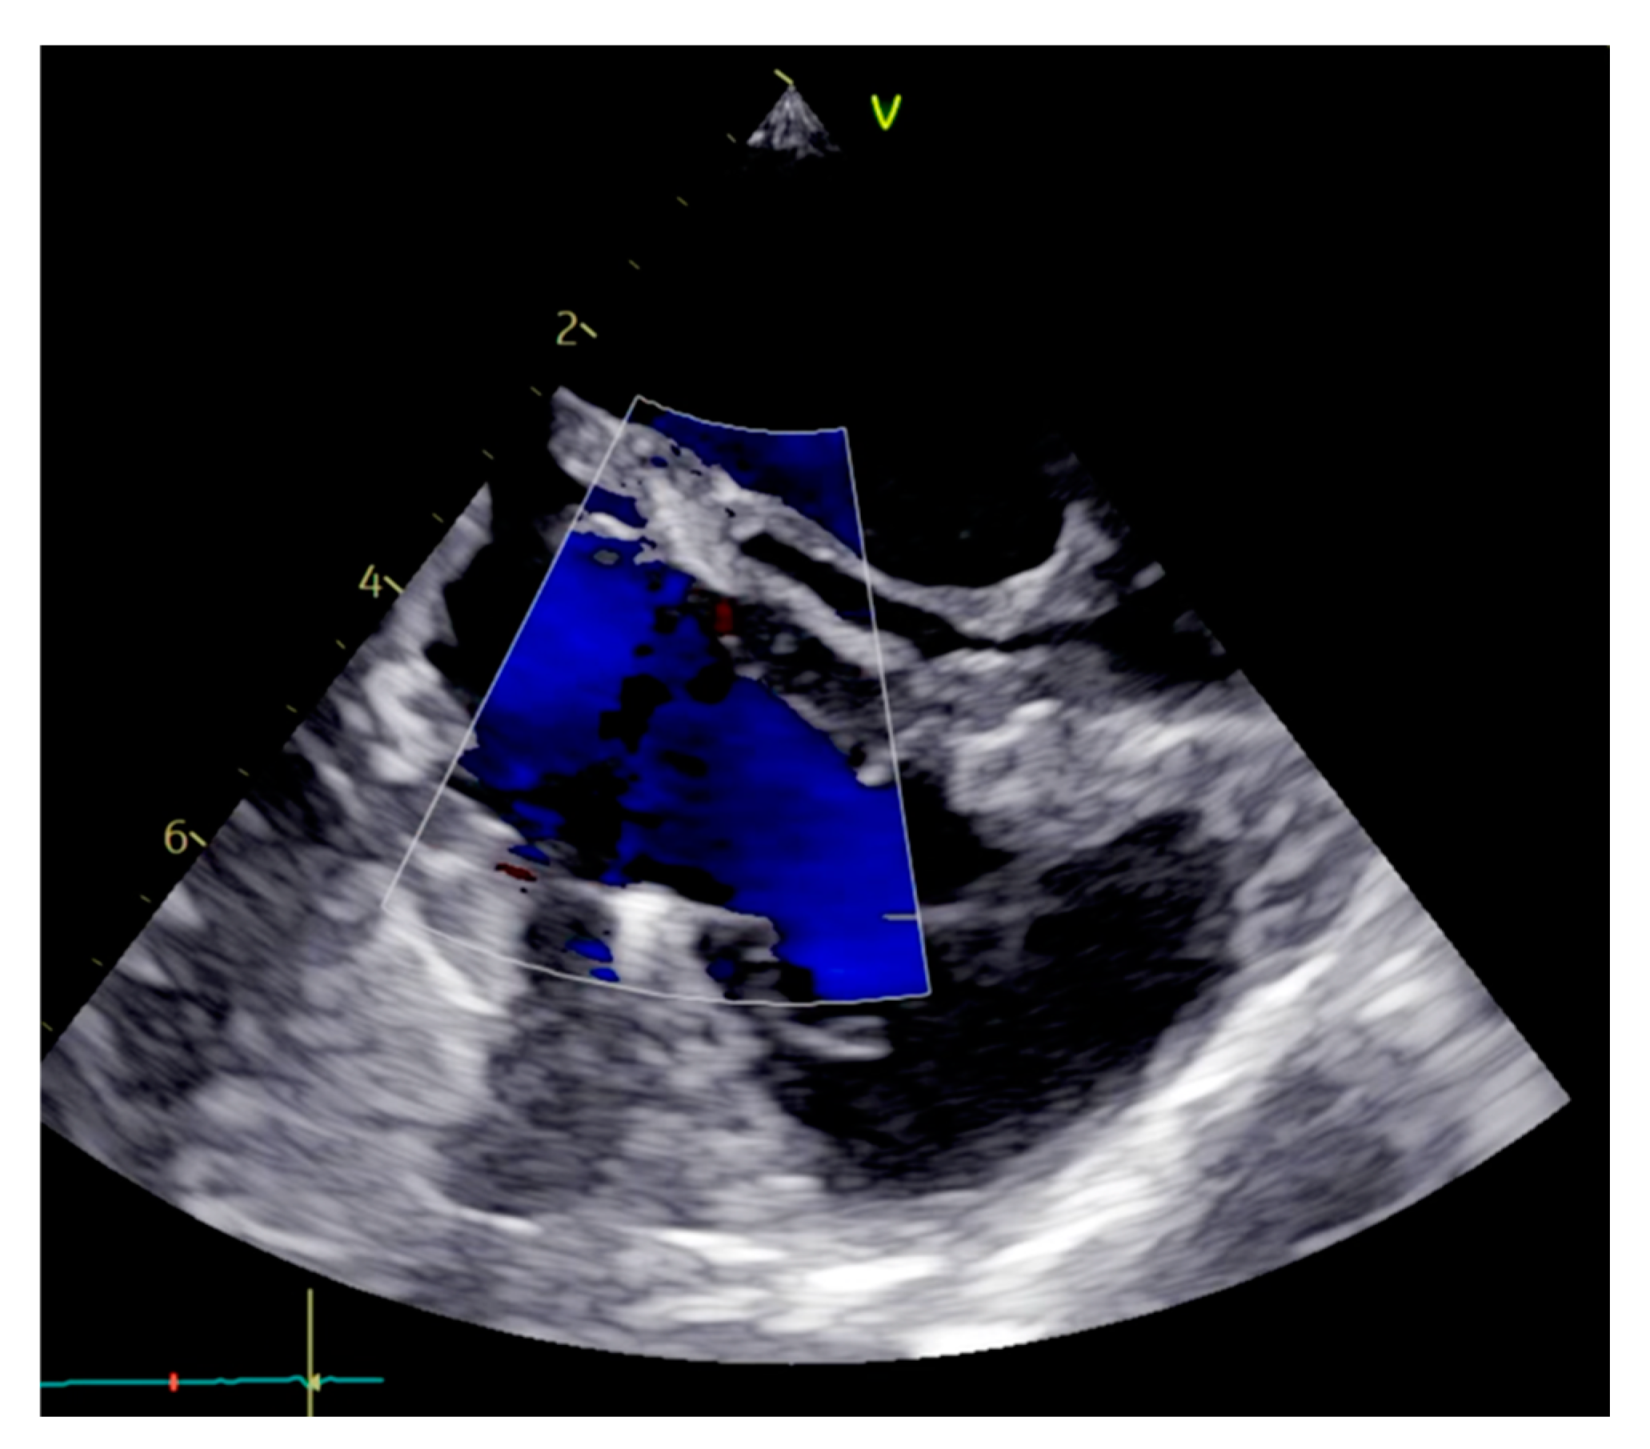

To achieve complete myxoma removal, the posterior leaflet chord was severed. Following the removal of the myxoma, the tip of the papillary muscle was resected. The tricuspid valve remained intact but exhibited insufficiency. The practitioners then decided to proceed with annuloplasty using a 30 mm Contour 3D annuloplasty ring (Medtronic, MN, USA). Subsequently, placement of 18 mm artificial chords (Seramon loops, Serag Wiessner, Naila, Germany) onto the posterior papillary muscle was carried out. The artificial chord was placed on the remnant non-fibrous part of the papillary muscle and two full-thickness bites were taken with pledgeted sutures. These four loops were then secured on the posterior and septal leaflets (Figure 5). The intraoperative echocardiography demonstrated valvular competence (Figure 6). The total duration of the operation was 198 min, with 70 min aortic of cross-clamping. During the procedure, the patient remained hemodynamically stable and was supported with 0.003 gamma noradrenaline. The patient was successfully extubated on the following day.

Figure 6. Post-operative transesophageal echocardiogram.